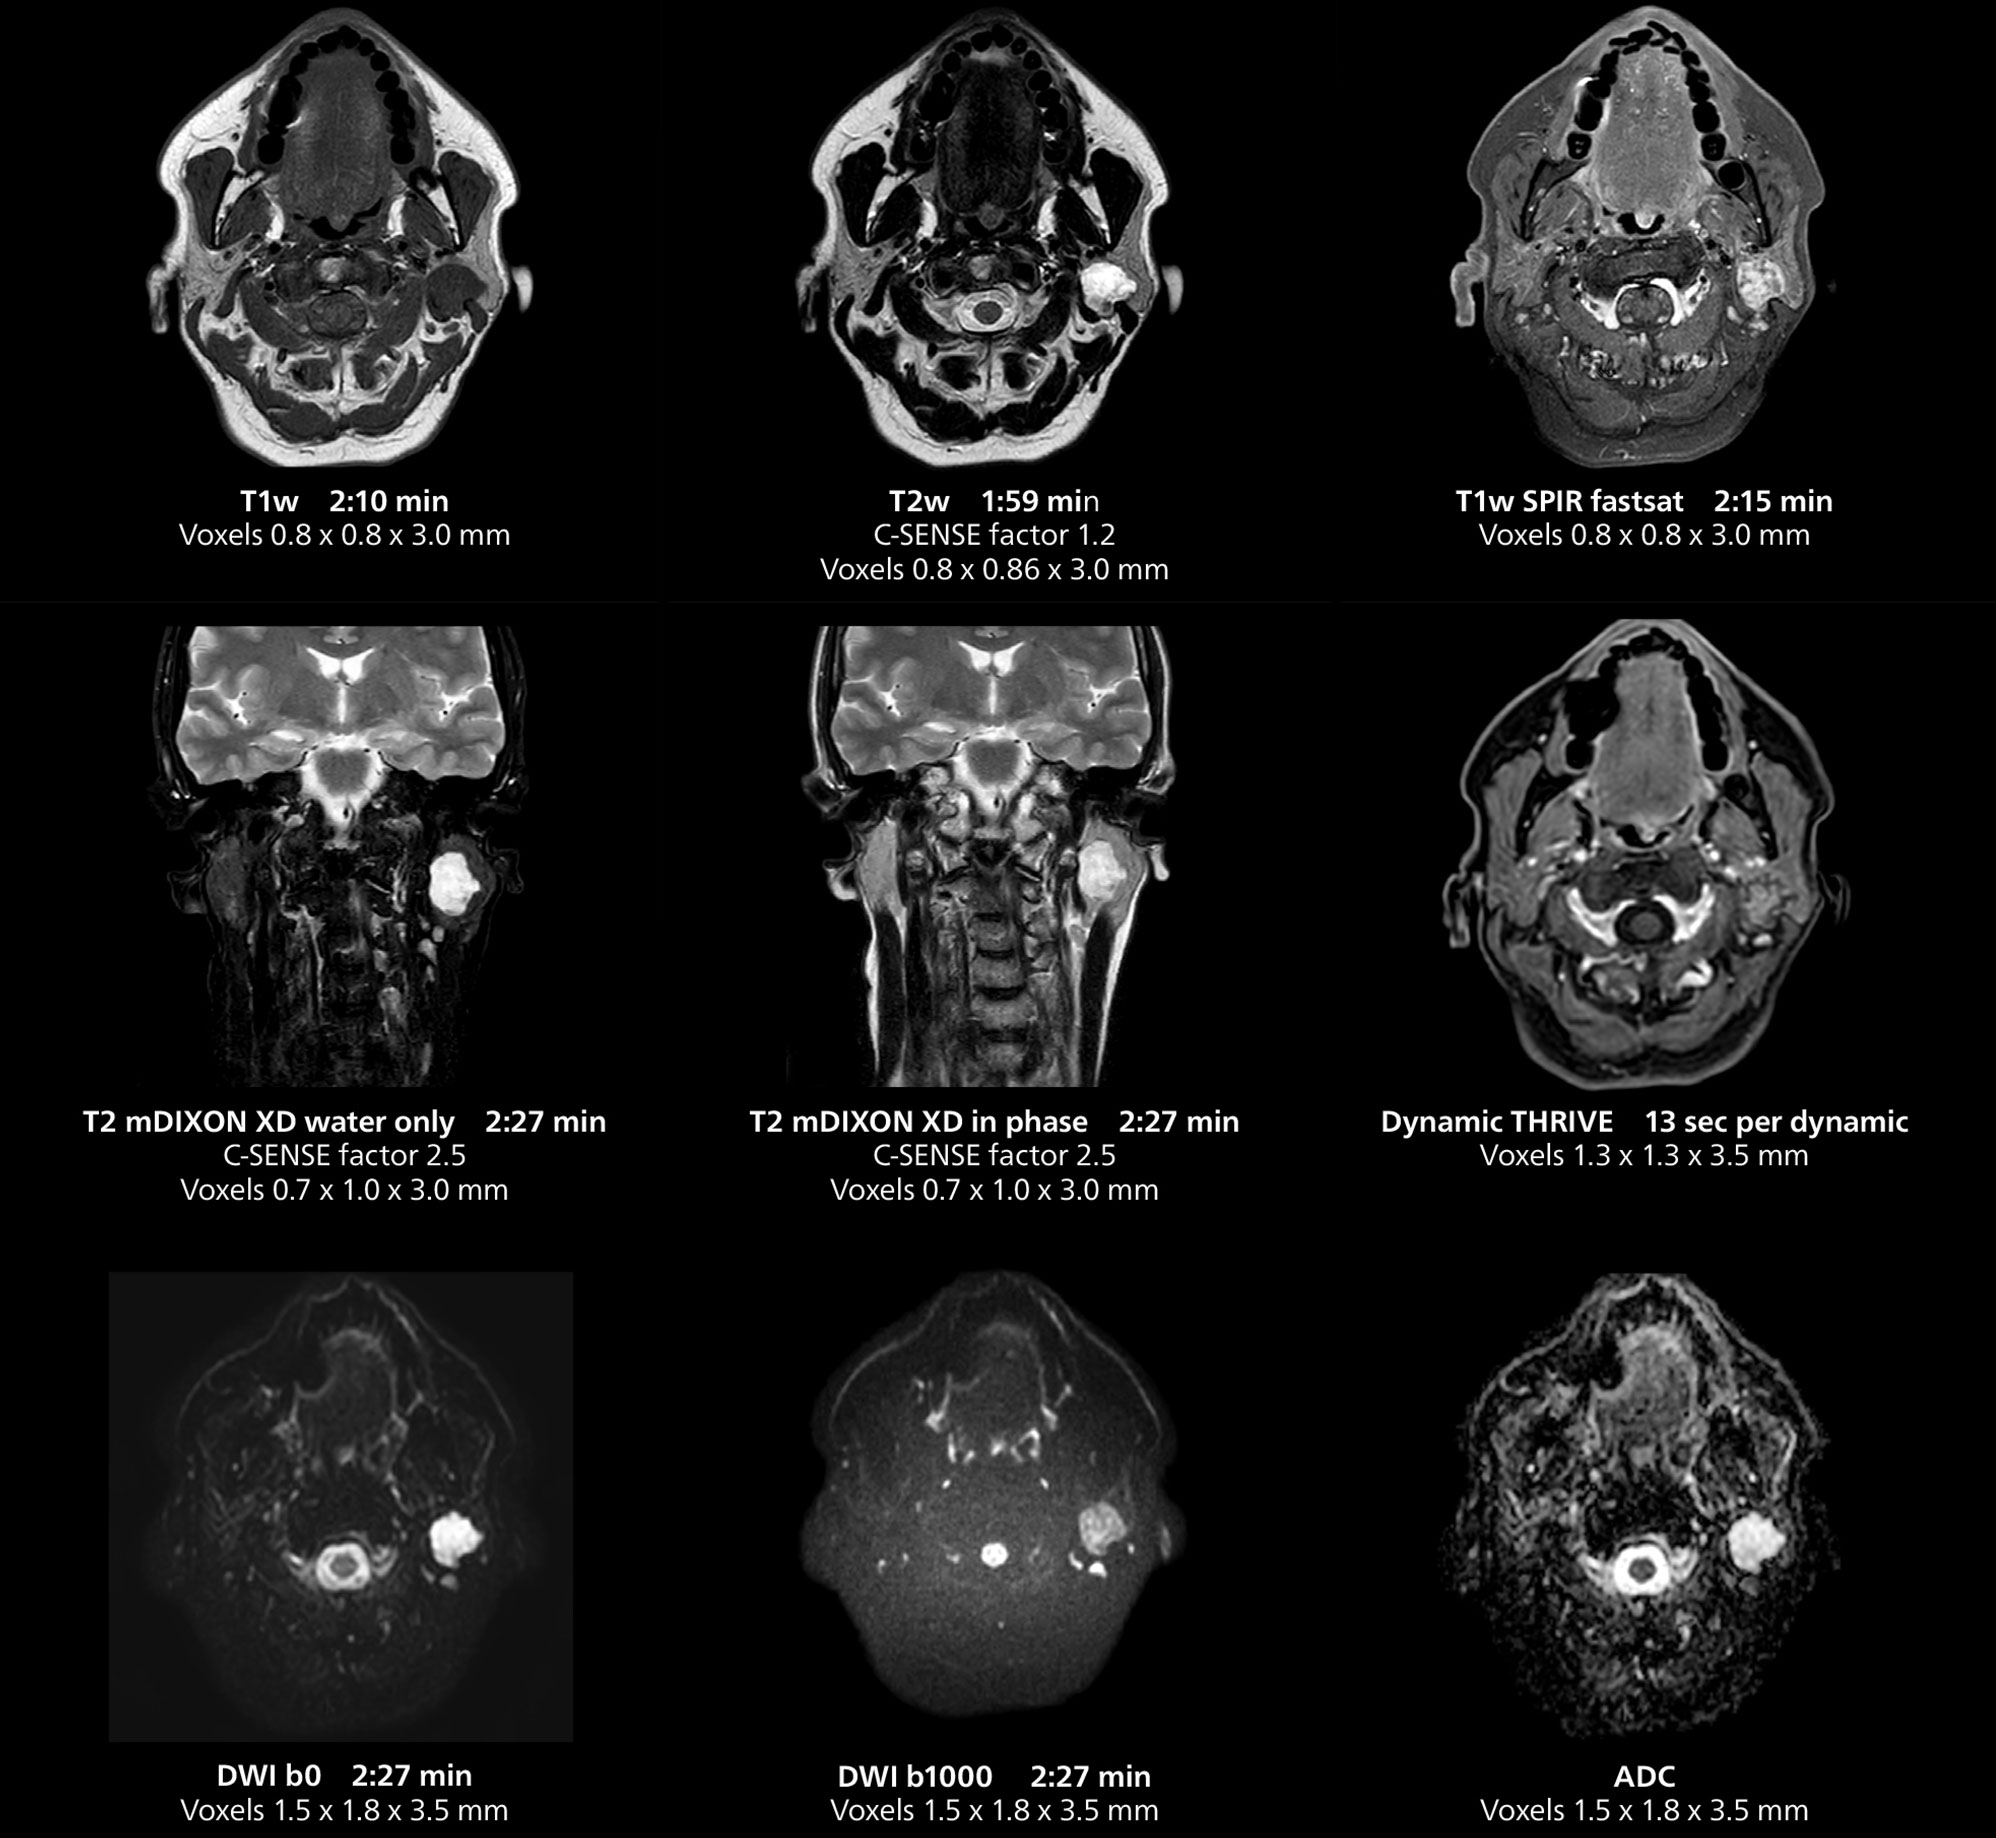

Salivary gland imaging on MR 5300

This MRI case illustrates imaging of salivary gland abnormalities with different sequences. Compressed SENSE allows to accelerate scanning while maintaining high quality. With mDIXON XD, different contrast types can be obtained from scanning one sequence.

Salivary gland imaging on MR 5300

This MRI case illustrates imaging of salivary gland abnormalities with different sequences. Compressed SENSE allows to accelerate scanning while maintaining high quality. With mDIXON XD, different contrast types can be obtained from scanning one sequence.